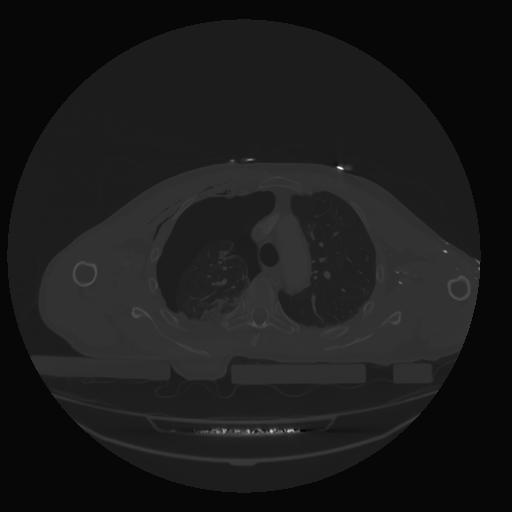

28 CUERPO,CE,Vol,2.0,CUERPO,,